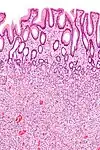

| Hyperplastic polyp | Colorectal (unless otherwise specified) | Serrated unbranched crypts | if polyps are more than 100 | ![]() |

Serrated polyposis syndrome |

| Hyperplastic polyp of the stomach | Stomach | Elongated, tortuous, and cystic foveolae separated by edematous and inflamed stroma.[4] | ![]() |

Gastric hyperplastic polyposis | |